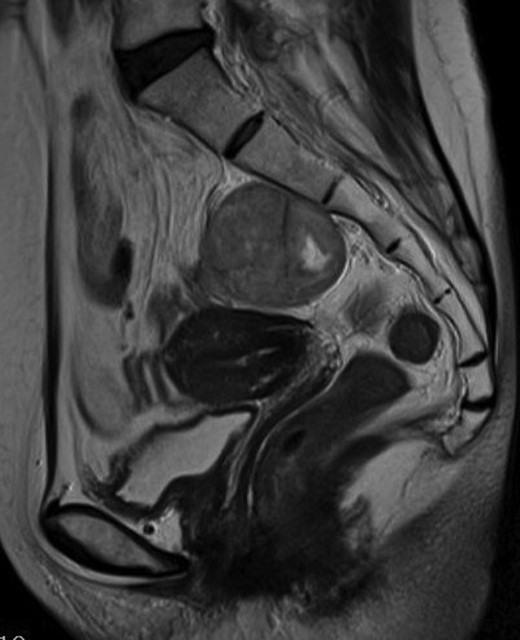

A 54-year-old woman was referred to our hospital with a mass in the pelvic cavity detected on chest-abdominal, CT done for investigation of breast cancer. She had no particular past and family history, and the physical examination was unremarkable. Ultrasonography of the pelvis revealed a 5 × 4.3 cm, solid mass separated from her right adnexa (Fig. 1). Contrast enhanced-CT showed a 5 × 4 cm, solid, well-defined, heterogeneous mass in the right side of the pelvic cavity (Fig. 2). MRI showed that the tumor demonstrated homogeneous hypointensity on T1-weighted images and heterogeneous slight hyperintensity on T2-weighted images (Fig. 3a and b). Sagittal sections of MRI demonstrated that the mass was intricately related to the anterior presacral fascia (Fig. 4). The preoperative diagnosis was a mesenteric gastrointestinal stromal tumor.

Sagittal MRI sections show the mass to be intricately related to the anterior presacral fascia.